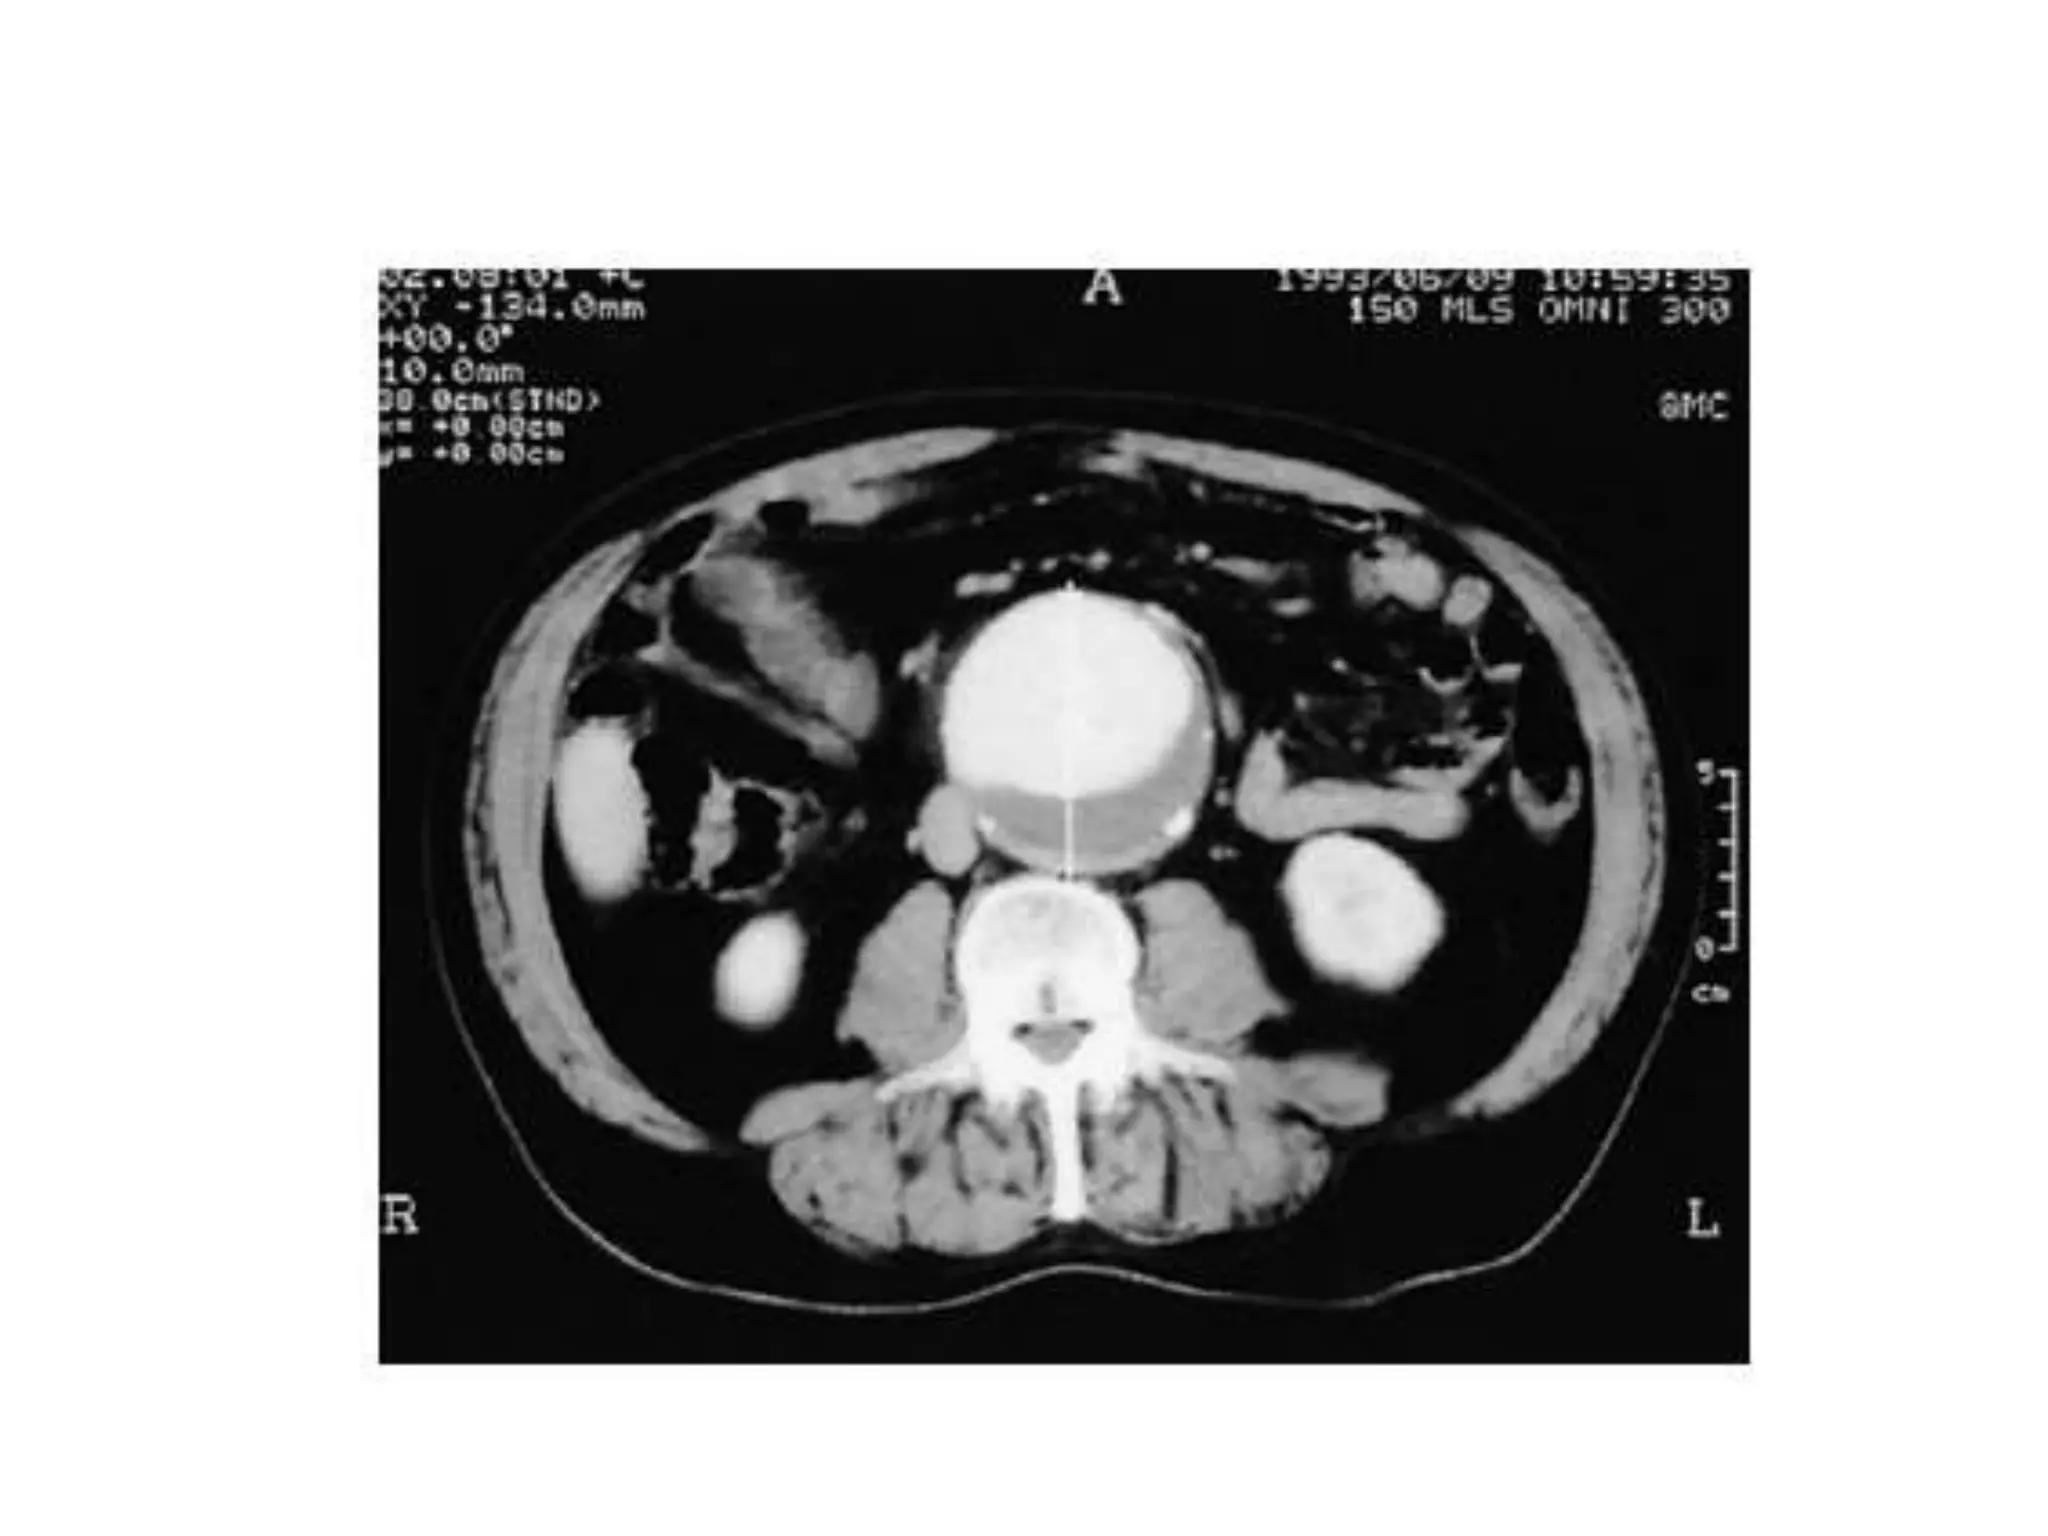

• CT SCAN:

– Shows the size of the aneurysm.

• CT SCAN: Best for assessing aneurysm

morphology.